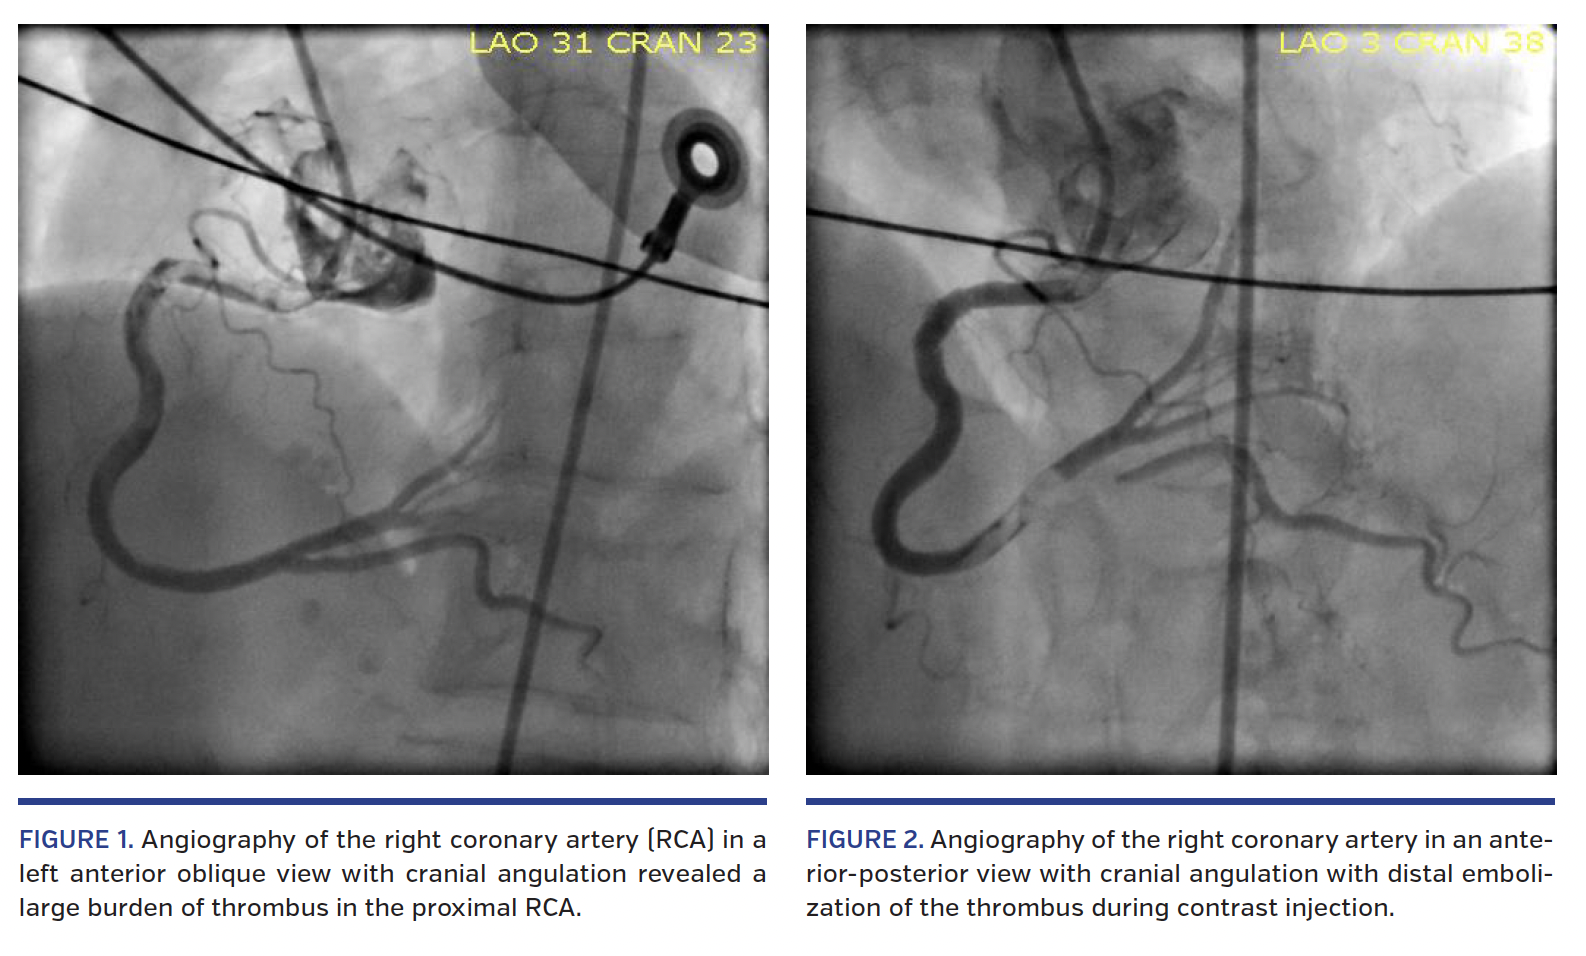

A 69-year-old woman with dementia, hypertension, hyperlipidemia, coronary artery disease, and prior percutaneous coronary intervention (PCI) of the right coronary artery (RCA) presented to the emergency department with syncope. Initial vital signs were notable for hypotension and bradycardia. Electrocardiography revealed sinus rhythm with complete atrioventricular block, a junctional escape rhythm, and 5 mm ST-segment elevations in the inferior leads, consistent with acute myocardial infarction. Loading doses of aspirin and ticagrelor were administered in the emergency department, and the patient was referred for emergent coronary angiography. Angiography of the RCA in a left anterior oblique view with cranial angulation revealed a large burden of thrombus in the proximal RCA (Figure 1) and distal embolization of the thrombus during contrast injection (Figure 2). Intravenous bivalirudin and cangrelor were immediately administered. Aspiration thrombectomy was performed with retrieval of the intact thrombus. Bradycardia and hypotension rapidly resolved. Balloon angioplasty was performed at the site of proximal RCA in-stent restenosis with improved angiographic appearance and TIMI 3 flow in the major branches at the conclusion of the case (Figure 3) (Video 1). The patient was transferred to the intensive care unit for further management.